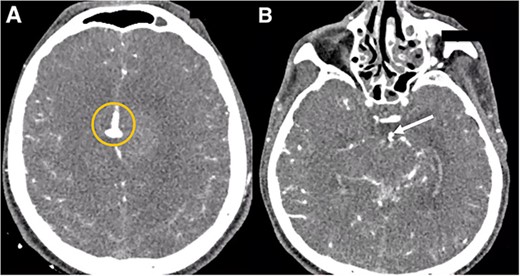

Brain imaging demonstrated improvement of the hematoma and intraventricular hemorrhage with remnant postinfarction areas (Fig. 4). The patient was transferred to neurointensive care postoperatively, where he remained for 7 days. At this point, the neurological examination indicated he had 4/5 quadriparesis, a right third nerve paresis, and a GCS score of 13. Seven days later, he was discharged with a modified Rankin scale (mRS) score of 4. At the 1-month follow-up, the patient had a GCS of 14 and a mRS of 4. At the 3-month follow-up, the patient showed a significant improvement in the GCS score with a mRS of 2 and improved function of the right third cranial nerve.

Postoperative head CT. (A, B) Sagittal and axial views show resolution of the hematoma and intraventricular hemorrhage with remaining postinfarction areas. (C–F) Postoperative head CT views depict the placement of clips in the accessory A2 artery (yellow arrow) and basilar aneurysm (green arrow).